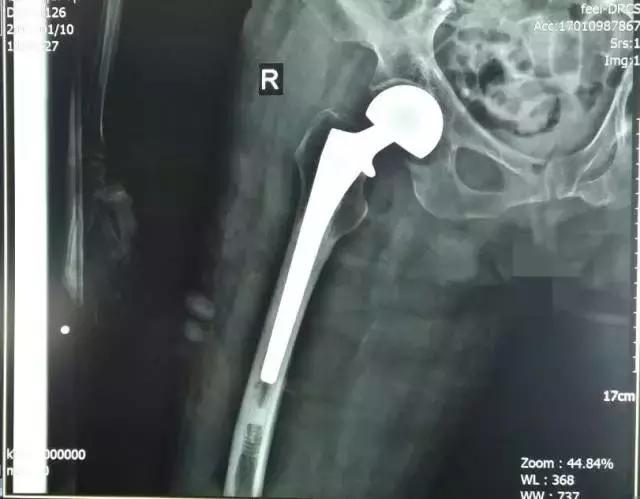

冷XX术前X线

冷XX术后X线

患者冷XX,男,86岁,患者因外伤致左髋部肿痛外展外旋畸形、左下肢活动受限4小时就诊。

入院诊断:1、左股骨粗隆间骨折;2、心脏搭桥术后;3、糖尿病;4、骨质疏松(重度)。

诊疗措施:患者因左股骨粗隆间骨折行左人工股骨头置换术。患者外伤史明确,保守治疗预后较差,后期严重影响生活质量。主治医师耐心与家属沟通病情,告知预后及风险,建议手术治疗,在患者及家属的配合下,成功进行了左股骨头置换术。术后患者左下肢功能恢复良好,同时也恢复了生活自理能力。